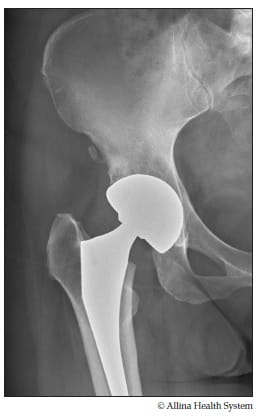

New hip x-ray

An X-ray shows the artificial joint (prosthesis).

The hip after a hip replacement

The hip replacement surgery removes damaged bone and cartilage from the hip joint and replaces it with an artificial joint (prosthesis). An artificial ball connected to a stem replaces the ball of your thigh bone. An artificial cup, shaped like a bowl, replaces the worn socket. These parts connect to create a new artificial hip that works almost like your own hip joint. All parts have smooth surfaces for comfortable movement once you have healed from the surgery.

Typically the prosthesis is made of a wear-resistant plastic (polyethylene) and a metal (titanium, tantalum or cobalt). The artificial ball and socket are held in place by bone cement, your bone growing into the prosthesis or a combination of both. Your surgeon will determine which prosthesis will work best for you.